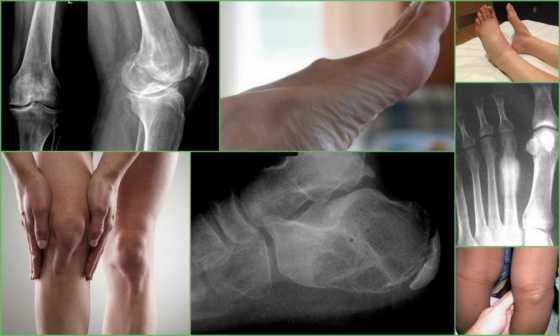

Ниже представлены фото кисты на ногах.

Разновидности кисты на ногах, внешние проявления и рентген

Методы диагностики

Диагностика кисты на ногах не представляет особых трудностей. В большинстве случаев достаточно внешней симптоматики. Для обнаружения глубоко расположенных новообразований применяется ультразвуковое или рентгенологическое обследование.

На снимке новообразование представляет собой полость, более темную, чем окружающие ткани. Это говорит о наличии в ней жидкости.